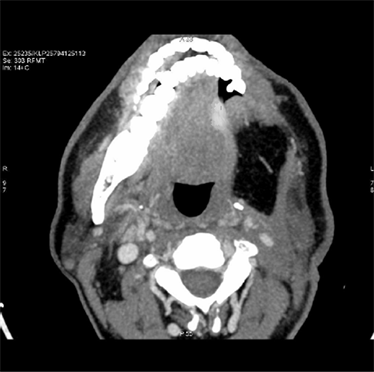

A 49-year male patient presented to outpatient department with a mass on the left lateral border of tongue associated with mild pain and enlarged lymph nodes on the left side of neck. He doesn’t have history of smoking or drinking. A plain computerised tomography (CT) scan done on 17/01/13 (Figure 1) revealed an irregular thickening of left lateral border of tongue with enlarged jugulo digastric lymph node measuring 1.8 × 1 cm. Bilateral level I and II nodes were positive. Patient was staged as T3, N2, M0. Excision of mass on the tongue was done and biopsy sent for histopathological examination which revealed infiltrating squamous cell carcinoma.

Pre-treatment CT scans show irregular thickening of left lateral border of tongue with enlarged jugulodigastric lymphnode.

Figure 1. Pre-treatment CT scan showing irregular thickening of left lateral border of tongue.